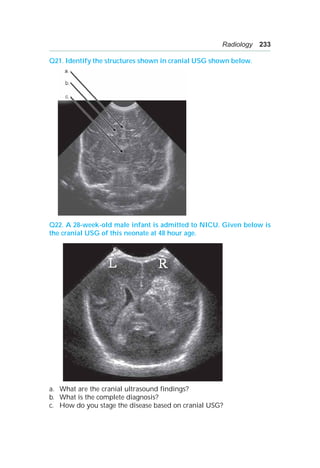

Neonatology 211 Q42. Aterm newborn was noted to have audible cranial bruit. Given below is the MRA of this neonate. a. What is the most likely diagnosis? b. List 2 most common complication associated with this condition. c. Name 1 treatment option. Q43. Given below is a picture of a 20-day-old term neonate. a. What is the sign seen in this photo? b. What is the pathophysiology of this sign? c. What is the most likely cause of this sign?

• 226.

212 OSCE inPediatrics Q44. An 8-month-old infant presented in paediatric OPD with severe seborrhoeic dermatitis and bilateral otitis media. There is history of recurrent fever and weight loss over past 2 months. On examination, he is noted to have axillary lymphadenopathy and hepatosplenomegaly. Given below is the X-ray of this infant. a. What is the finding seen on the chest X-ray? b. What is the most likely diagnosis? c. What is the treatment in this patient? Q45. Given below is the X-ray of term neonate who was born via elective LSCS. a. List 3 findings seen on X-ray. b. What is the most likely diagnosis? c. What are the clinical findings likely to be seen in this neonate?

• 227.

Neonatology 213 Q46. Amale newborn was born at 28 week gestation. He is now 4 weeks old and has needed 4 packed red cell transfusions. His current Hb is 6.8 mg/dL with low reticulocyte count. He is on full enteral feeds and iron (4 mg/kg/day) for past 10 days. a. What is the most likely diagnosis? b. What medication could have decreased the need for frequent blood transfusions in this neonate? c. Give one non-hematological advantage of this medication. Q47. A term neonate is noted to have petechiae and purpura all over the body on day 2 of life. His platelet counts are noted to be 60,000/mm3. Mother is a primigravida and known case of SLE. Her platelet counts are 70,000/mm3. a. What is the most likely diagnosis in this newborn? b. Enlist 2 generally accepted criteria for platelet transfusion in case of neonatal thrombocytopenia. c. How do you define neonatal thrombocytopenia? d. What is the treatment? Q48. A 3 kg term ventilated neonate is nil by mouth. He is on 10% dextrose at rate of 9 ml/hr. a. What is formula for calculating glucose infusion rate (GIR)? b. Calculate the GIR for this baby. c. What is the minimum GIR requirement of a neonate? Q49. A 30-week female infant is about to be delivered via emergency LSCS in view of severe oilgohydramnios. The serial scans since 20 weeks have shown oligohydramnios. a. Enlist 2 most common causes of oilgohydramnios. b. Give 1 serious complication which might be seen on delivery of this neonate.